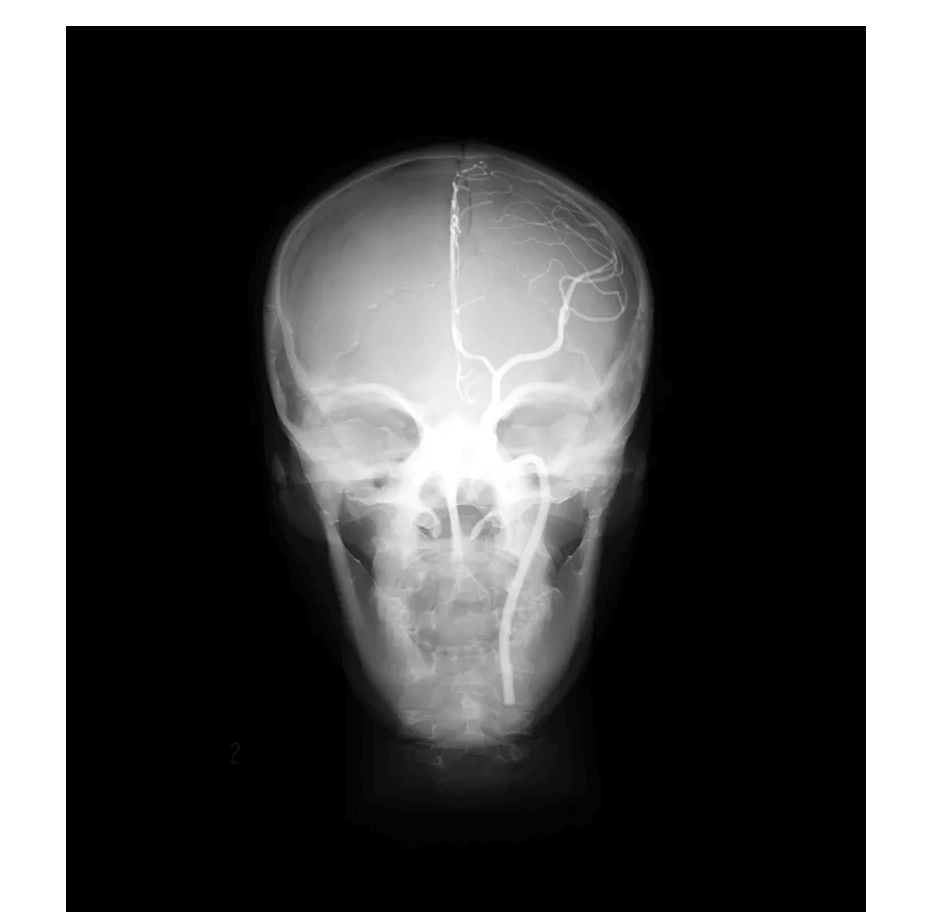

Das Angiographie Kopfmodell ist ein hochpräzises Trainingsmodell, das einen synthetischen Schädel in einen Kunststoffkopf integriert. In der linken Schädelhälfte sind die vordere und mittlere Hirnarterie nachgebildet und mit Kontrastmittel gefüllt, um realistische Trainingsbedingungen für die Angiographie zu schaffen. Die simulierten Arterien haben einen Durchmesser von 0,5 mm bis 4 mm und ermöglichen so eine detaillierte Untersuchung und Diagnose von Gefäßstrukturen im Gehirn. Dieses Modell ist besonders geeignet für medizinische Fachkräfte, die ihre Fähigkeiten in der Angiographie und Bildgebung von Gehirngefäßen verbessern möchten.

Präzise Nachbildung der vorderen und mittleren Hirnarterien im synthetischen Schädel

Arterien mit Durchmessern von 0,5 mm bis 4 mm für detaillierte Bildgebungstraining

Mit Kontrastmittel gefüllte Arterien ermöglichen realistische Angiographie-Simulationen

Das Modell ist für den Einsatz in der Angiographie und der Gefäßdiagnostik ausgelegt, insbesondere für das Training der Bildgebungstechniken in der neurologischen Radiologie.